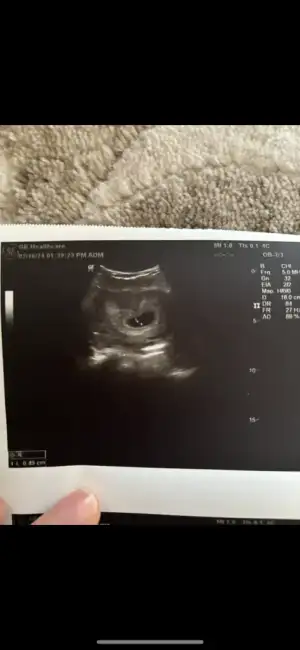

Kızlar iyi geceler hepinize. Bugün ilk kontrolüme gittim kalp atışını duyduk adet tarihim ile uyumlu çıktı. 6+2 dedi progestan verdi ağrım çok var diyince.